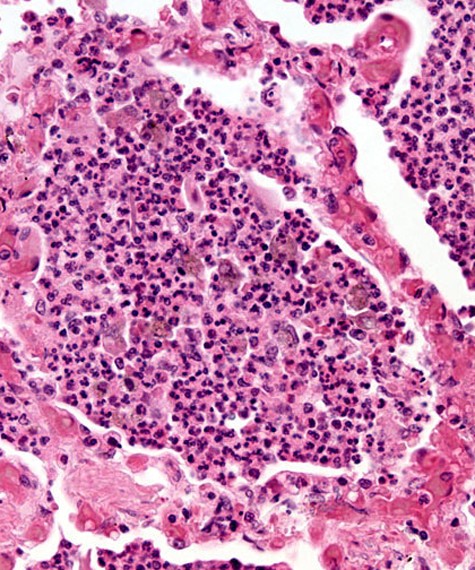

Upon taking my patient's history, I found that Amina presented with intermittent fever, headache, loss of appetite, weakness, and leg swelling. I requested a Rapid Diagnostic Test (RDT) and blood count. The RDT came back positive and the blood count indicated severe anemia. I prescribed Amina Artemether-Lumefantrine, which is an anti-malarial tablet, and iron tablets for her anemia. In addition to this, I advised her to wear long sleeves, pants and to sleep using an insecticide-treated mosquito net to prevent catching malaria again, as well as maintaining a balanced, nutritious, and iron-rich diet to prevent nutritional anemia in the future.

Amina was ultimately diagnosed with malaria and anemia. She was placed on antimalarial drugs and iron tablets.